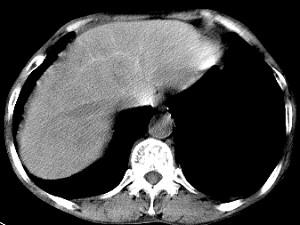

问题 男,40岁有血吸虫感染史,腹胀不适,食欲减退,CT扫描所见如图,最可能的诊断是 ( )

选项 A.肝炎后肝硬化 B.血吸虫后肝硬化 C.酒精性肝硬化 D.胆汁性肝硬化 E.脂肪肝

答案 B